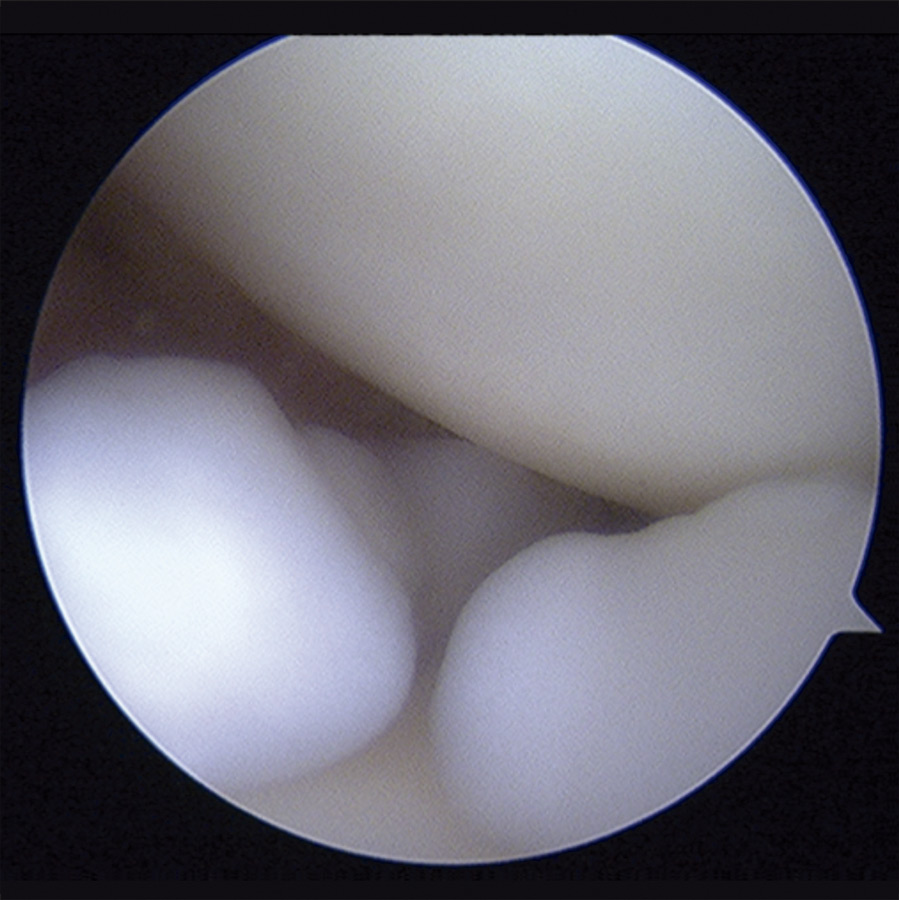

Con el diagnóstico de condromatosis sinovial de hombro derecho se procedió a la realización de una artroscopia, viendo múltiples cuerpos libres intraarticulares, la mayoría de ellos de consistencia cartilaginosa (Figuras 3 y 4) y se procedió a su extracción por vía artroscópica (Figura 5). Tras la cirugía, se remitió a la paciente a recuperación funcional, presentando una buena evolución clínica. La paciente se encuentra asintomática en el momento actual, presentando un balance articular completo.

Figura 3. Imagen artroscópica: cuerpos libres en condromatosis sinovial.

Figura 4. Imagen artroscópica: cuerpos libres en condromatosis sinovial.